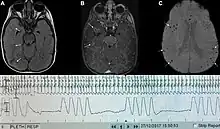

| Graph showing Biot's respiration and other pathological breathing patterns. | |